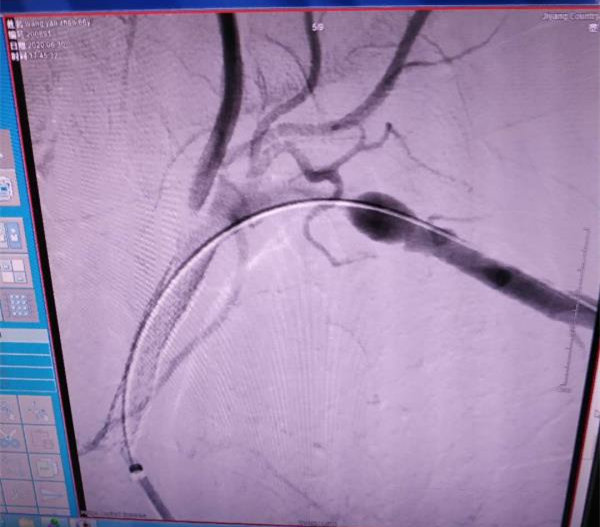

手术过程非常复杂,手术医师首先尝试经股动脉途径,使用各种导丝均未能通过闭塞病变;后改左桡动脉途径,反复尝试后导丝最终通过闭塞病变,并证实在血管真腔,然后选用不同大小的球囊扩张闭塞段血管,再从股动脉途径导入加硬导丝及输送鞘,最终成功置入支架,患者闭塞的左锁骨下动脉被重新开通。术后患者左上肢血运明显改善,酸胀感消失,患者及家属对手术效果很是满意。

此种疾病以往只能采取保守治疗,治疗效果差,不能解除患者痛苦。锁骨下动脉球囊扩张+支架植入术在我院尚属首次开展,具有创伤小、恢复快、效果显著等优点,因此在锁骨下动脉闭塞疾病的治疗中被临床广泛应用。此例手术的成功开展标志着医院治疗复杂血管病变的技术水平再次迈向新台阶。